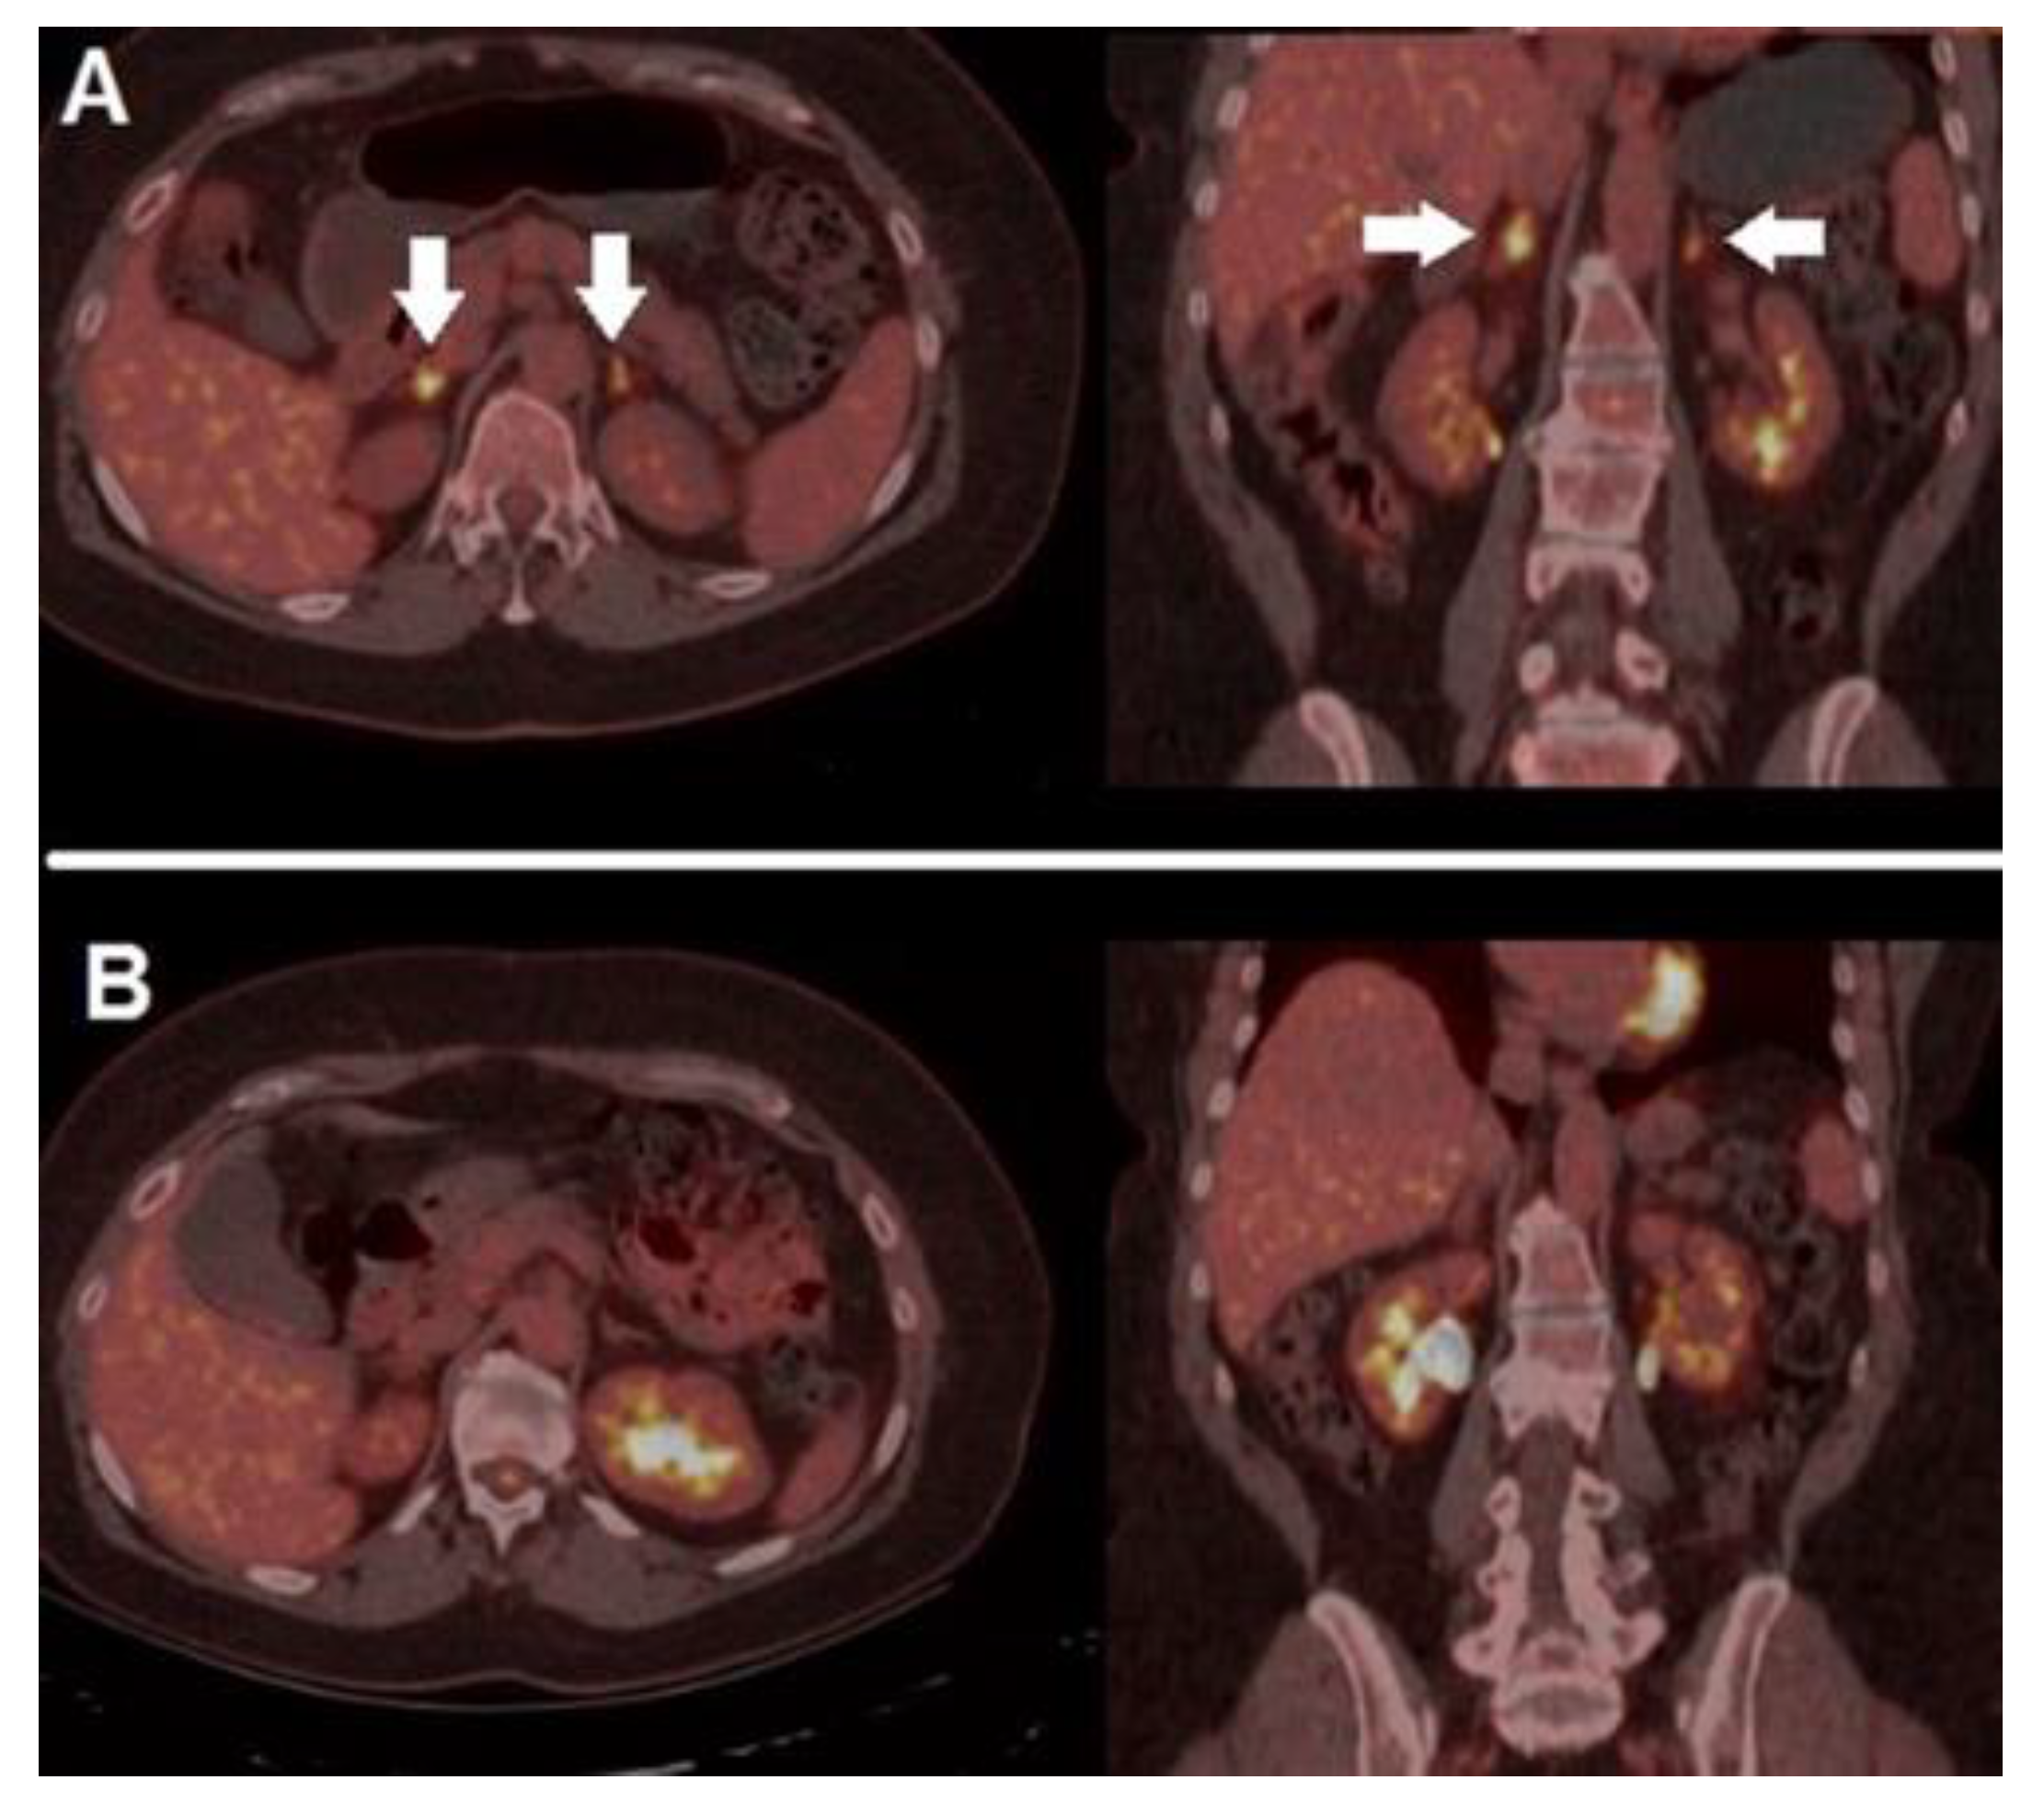

- Schmitt, R.J.; Kreidler, S.M.; Glueck, D.H.; Amaria, R.N.; Gonzalez, R.; Lewis, K.; Bagrosky, B.M.; Kwak, J.J.; Koo, P.J. Correlation between Early 18F-FDG PET/CT Response to BRAF and MEK Inhibition and Survival in Patients with BRAF-Mutant Metastatic Melanoma. Nucl. Med. Commun. 2016, 37, 122–128. [Google Scholar] [CrossRef][Green Version]

- Annovazzi, A.; Ferraresi, V.; Rea, S.; Russillo, M.; Renna, D.; Carpano, S.; Sciuto, R. Prognostic Value of Total Metabolic Tumour Volume and Therapy-Response Assessment by [18F]FDG PET/CT in Patients with Metastatic Melanoma Treated with BRAF/MEK Inhibitors. Eur. Radiol. 2021. head of print. [Google Scholar] [CrossRef]

- Wahl, R.L.; Jacene, H.; Kasamon, Y.; Lodge, M.A. From RECIST to PERCIST: Evolving Considerations for PET Response Criteria in Solid Tumors. J. Nucl. Med. 2009, 50, 122S–150S. [Google Scholar] [CrossRef]

- Sachpekidis, C.; Larribere, L.; Pan, L.; Haberkorn, U.; Dimitrakopoulou-Strauss, A.; Hassel, J.C. Predictive Value of Early 18F-FDG PET/CT Studies for Treatment Response Evaluation to Ipilimumab in Metastatic Melanoma: Preliminary Results of an Ongoing Study. Eur. J. Nucl. Med. Mol. Imaging 2015, 42, 386–396. [Google Scholar] [CrossRef]

- Anwar, H.; Sachpekidis, C.; Winkler, J.; Kopp-Schneider, A.; Haberkorn, U.; Hassel, J.C.; Dimitrakopoulou-Strauss, A. Absolute Number of New Lesions on 18F-FDG PET/CT Is More Predictive of Clinical Response than SUV Changes in Metastatic Melanoma Patients Receiving Ipilimumab. Eur. J. Nucl Med. Mol. Imaging 2018, 45, 376–383. [Google Scholar] [CrossRef]

| Wahl et al. [47] | 2009 | PERCIST | Complete regression of all 18F-FDG-avid sites | SULpeak reduction in at least 30% in the target lesions | Increase in SULpeak of at least 30% or new lesions | None of the previously mentioned conditions |

| Sachpekidis et al. [48] | 2015 | EORTC | Complete regression of all 18F-FDG-avid sites | Minimum reduction of ±15–25% in SUV after the 1st cycle of chemotherapy, and >25% after more than one cycle | Increased SUVmax of ≥25% or appearance of new lesions | None of the previously mentioned conditions |

| Anwar et al. [49] | 2018 | PERCIMT | No new lesions (Clinical Benefit) | No new lesions (Clinical Benefit) | >4 new lesions with functional DM <1 cm, or three new lesions with functional diameter >1 cm or two new lesions with functional diameter >1.5 cm | None of the previously mentioned conditions |

| Goldfarb et al. [50] Filippi et al. [51] | 2019 2022 | iPERCIST | Complete regression of all 18F-FDG-avid sites | SULpeak reduction of at least 30% in the target lesions | Increase in SULpeak of at least 30% or new lesions (unconfirmed progressive disease/UPMD), needing confirmation (cPMD) with a further scan after 4–8 weeks. | None of the previously mentioned conditions |

| Ito et al. [52] | 2019 | Immunotherapy-modified PERCIST (imPERCIST5) | Complete regression of all 18F-FDG-avid sites | Sum of SULpeak decreased by at least 30% | Increase in the sum of SULpeak by at least 30% | None of the previously mentioned conditions |